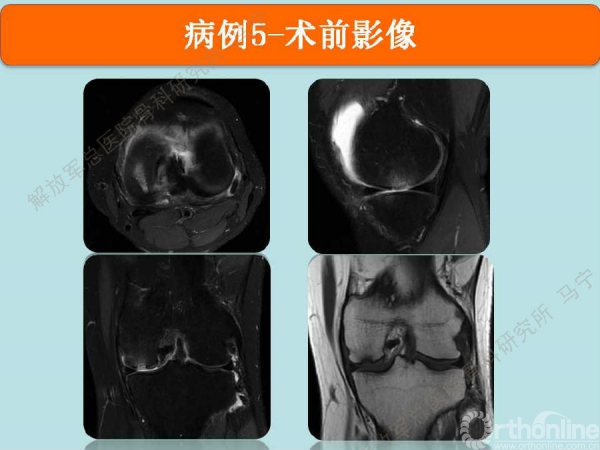

病例5

陈某,男,31岁,足球训练伤。

术中显示损伤部位及第四代组织工程软骨修补术后。术后三个月核磁显示组织工程软骨具备一定厚度,胶原含水量接近正常,还存在GAP现象。随访还在进行中。